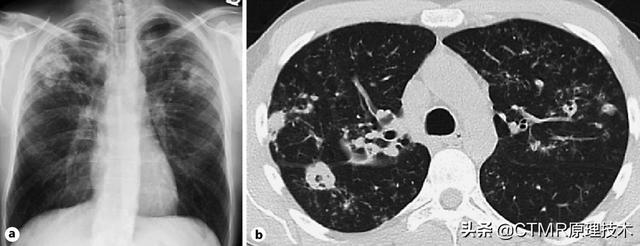

CT在医学影像领域指计算机体层摄影,全称是ComputedTomography,是20世纪最伟大的发明之一。我们都知道放射科的X线光片,拍出来的大多是人体一个骨骼的投影,是一个重叠的影像。我们先来理解下X光片是怎么产生的。...